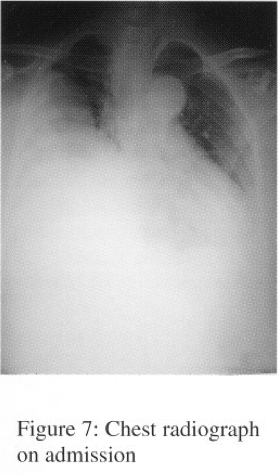

In Sept 2003, she was admitted to NDH for progressive dyspnoea and cough. CXR showed huge right lung opacity with right sided pleural effusion (Serial CXRs shown on figures 1-3).

Chest radiograph is the most important radiological tool for evaluation of SFT. It appears as a well-defined, homogeneous, and rounded mass on CXR. Pedunculated form of SFT has been reported to be moving on successive CXRs. Pleural effusion occurs in 8 – 17%, especially associated with malignant SFT. Calcifications are present in 7% of the tumour.